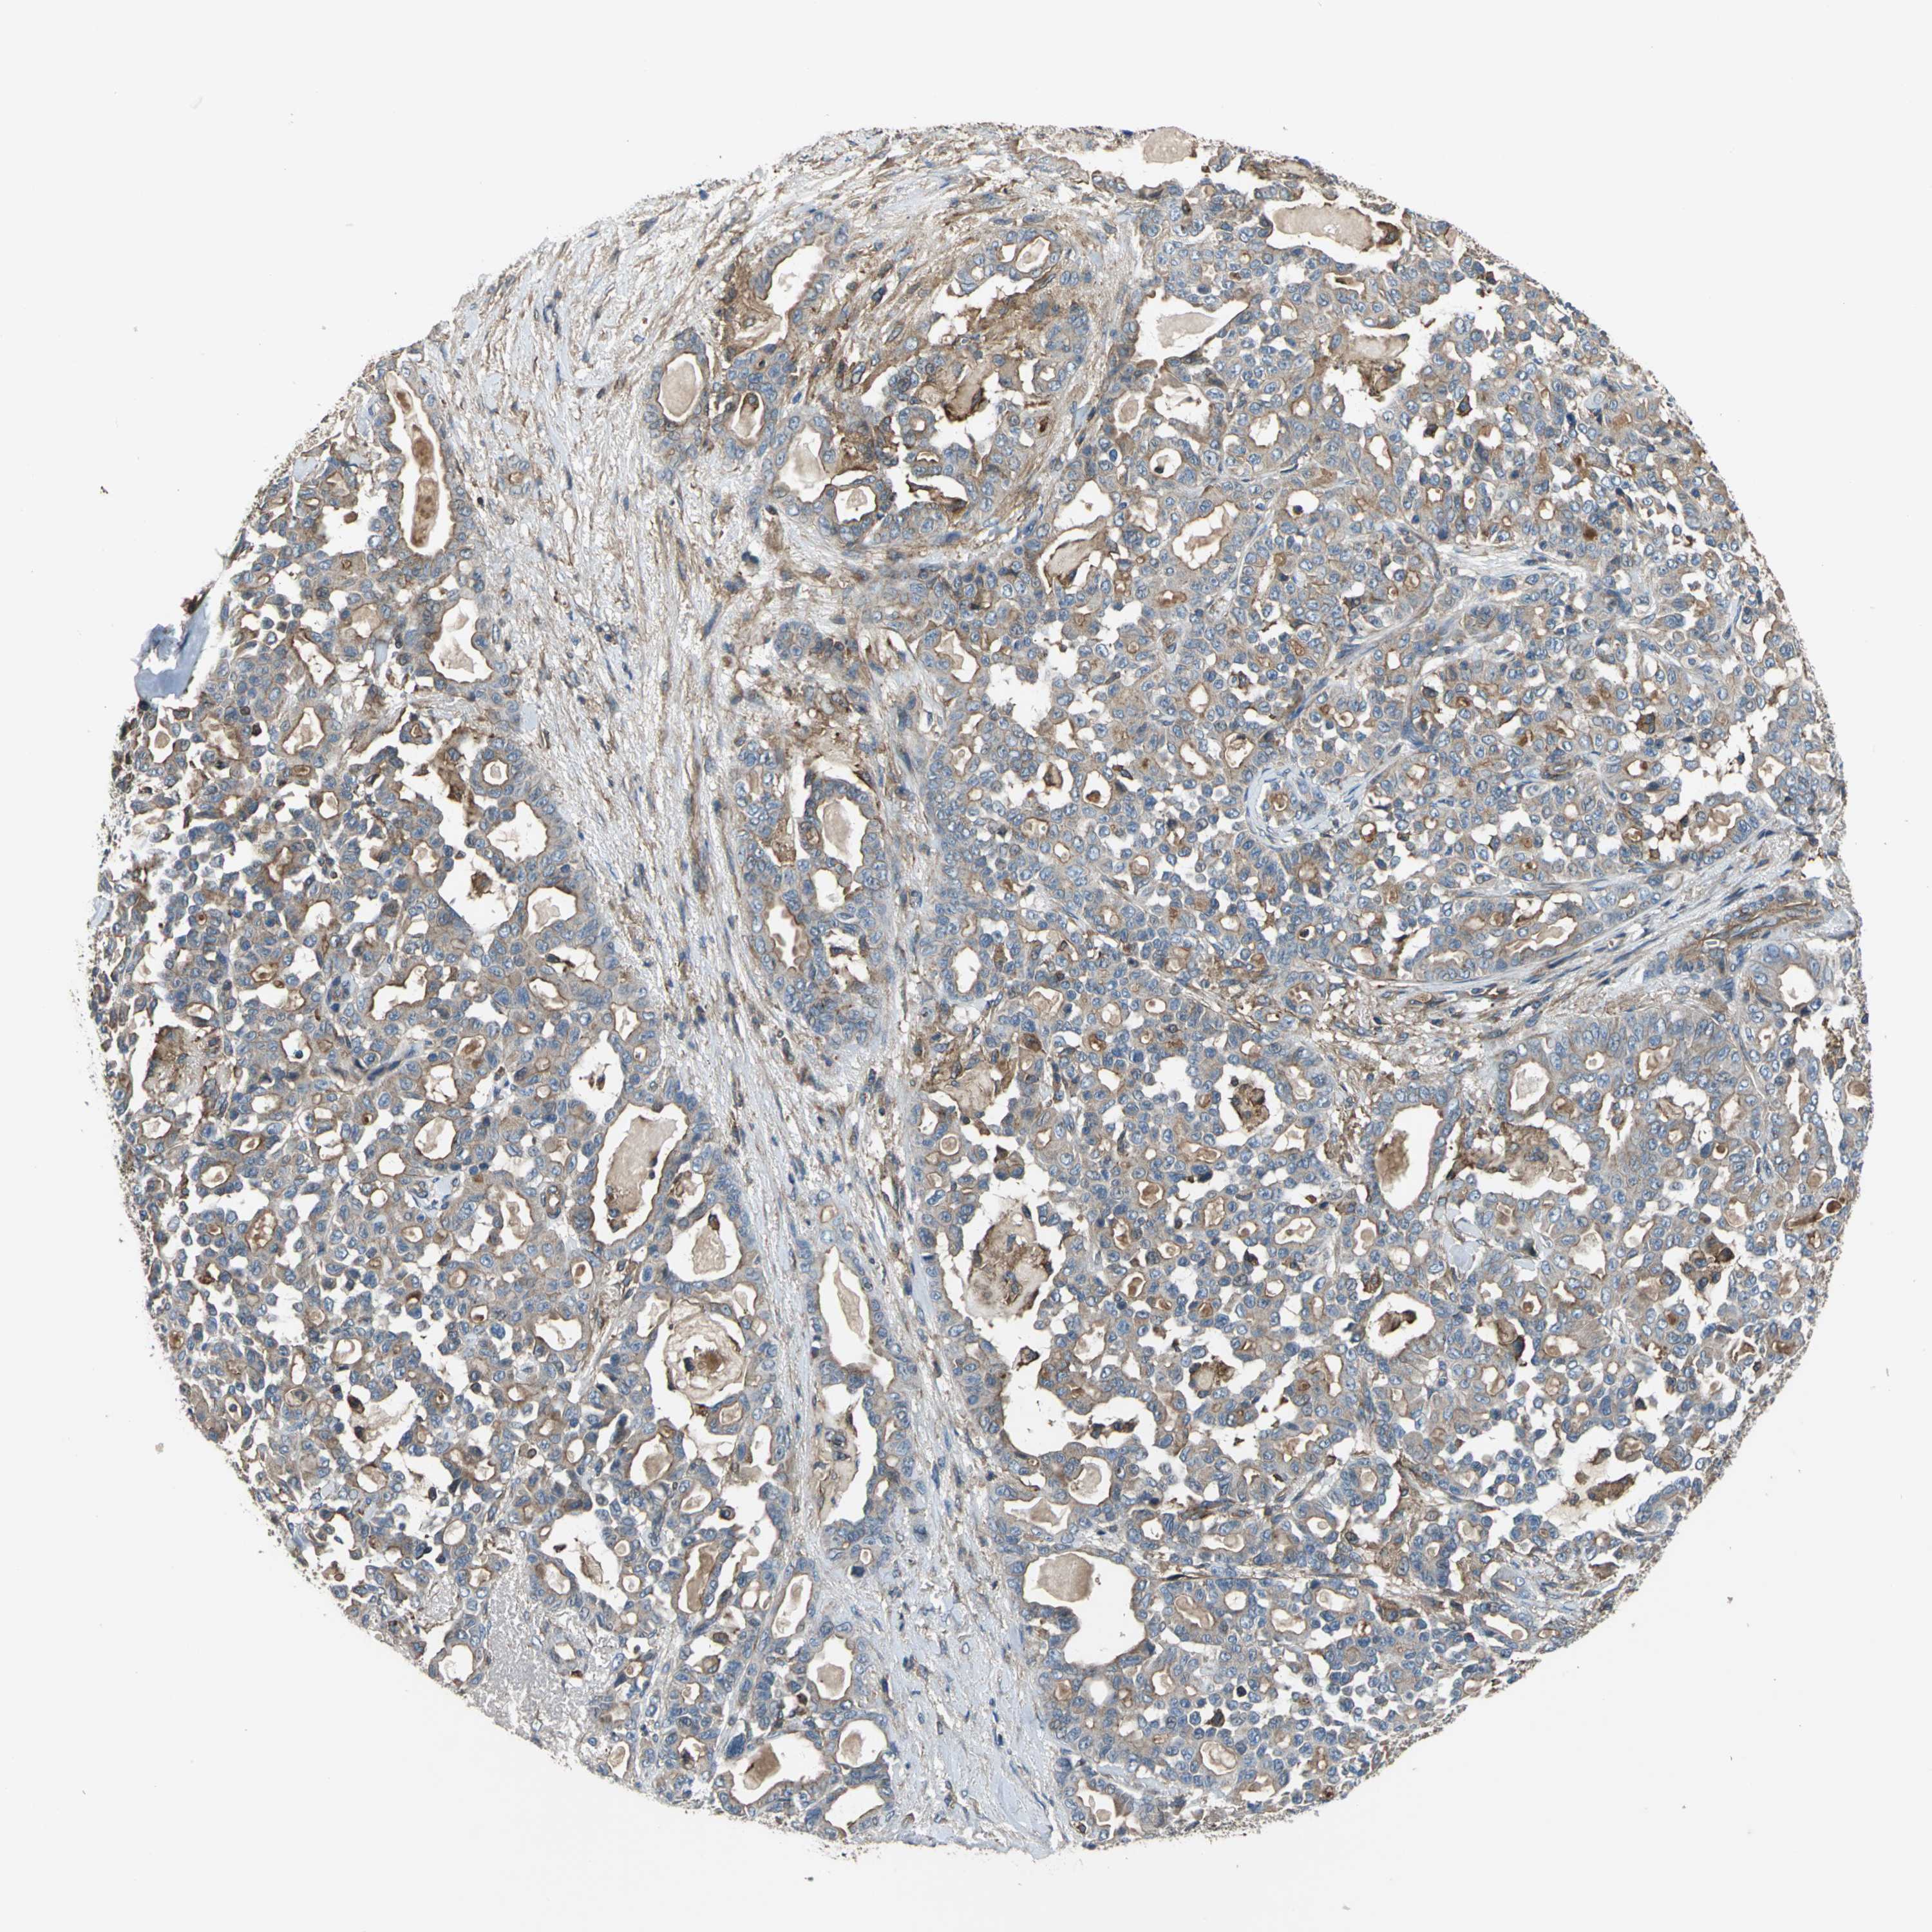

PANCREATIC CANCER - Protein expressioni

A mouse-over function shows sample information and annotation data. Click on an image to view it in a full screen mode. Samples can be filtered based on level of antibody staining by selecting one or several of the following categories: high, medium, low and not detected. The assay and annotation is described here.

Note that samples used for immunohistochemistry by the Human Protein Atlas do not correspond to samples in the TCGA dataset.

Antibody stainingi

Antibody staining in the annotated cell types in the current human tissue is reported as not detected, low, medium, or high, based on conventional immunohistochemistry profiling in selected tissues. This score is based on the combination of the staining intensity and fraction of stained cells.

Each image is clickable and will lead to virtual microscopy that enables deeper exploration of all samples and also displays staining intensity scores, fraction scores and subcellular localization as well as patient and tissue information for each sample.

Antibody HPA005964

Staining

High

Medium

Low

Not detected

Intensity

Strong

Moderate

Weak

Negative

Quantity

>75%

75%-25%

<25%

None

Location

Nuclear

Cytoplasmic/membranous

Cytoplasmic/membranous,nuclear

Adenocarcinoma, NOS

Adenocarcinoma, metastatic, NOS